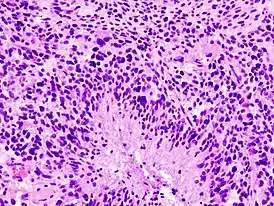

Астроцитома поддаётся диагностике, удаляют её только хирургическим путём. Для обнаружения опухоли делают компьютерную томографию (КТ) и магнитно-резонансную томографию (МРТ). При подозрении на опухоль обязательно проводят биопсию. Для этого вскрывают череп, затем забирают образец ткани мозга, который изучают под микроскопом на наличие опухолевых клеток, и если они обнаружены, то удаляется как можно большая часть опухоли[2].